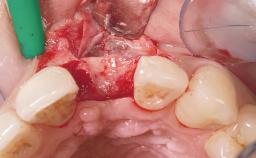

A 36-year-old female patient was referred for the replacement of the upper left central incisor (tooth 21), which had fractured. Although the tooth had been asymptomatic for many years, the crown began to loosen, at which time she presented to her dentist for an assessment. Teeth 21 and 22 had both been endodontically treated many years previously. She was a healthy individual and a non-smoker.